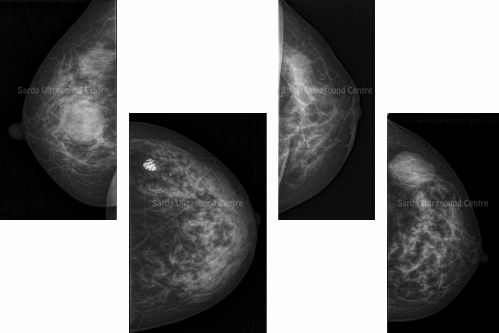

Regular screening, early detection and timely further workup are essential in early detection and treatment of breast cancer. We are equipped with Siemens Nova 3000 mammography machine which is known for its quality and details.